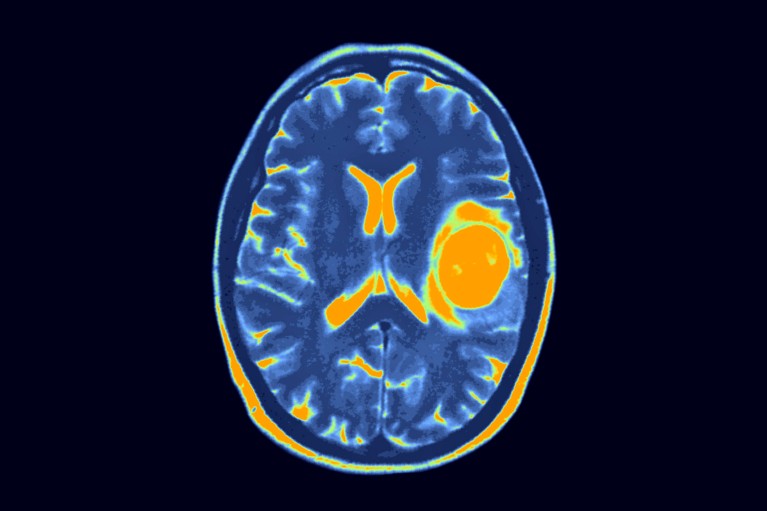

Brain Tumours

Brain tumours in children and young adults are not common.

However, 25% of childhood cancers are in the brain. There are many types of brain tumours that occur more commonly in children, such as medulloblastoma, glioma, ependymoma, craniopharyngioma, and embryonal tumours. Early detection and management of these brain tumours can improve outcome.